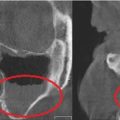

| Гранулематозное воспаление (гранулематоз Вегенера) | Аутоиммунное заболевание, при котором вырабатываются антитела к собственным здоровым клеткам организма | ![]() |

Ограниченное или распространенное утолщение перегородки, ее изъязвление и перфорация в околоносовые пазухи, утолщение костных стенок |

| Мукоцеле (слизистая киста) околоносовых пазух | Кистозное образование, как следствие закупорки выводных протоков | ![]() |

Снижение воздушности, изменение формы и размеров пазухи, истончение образующих стенок |